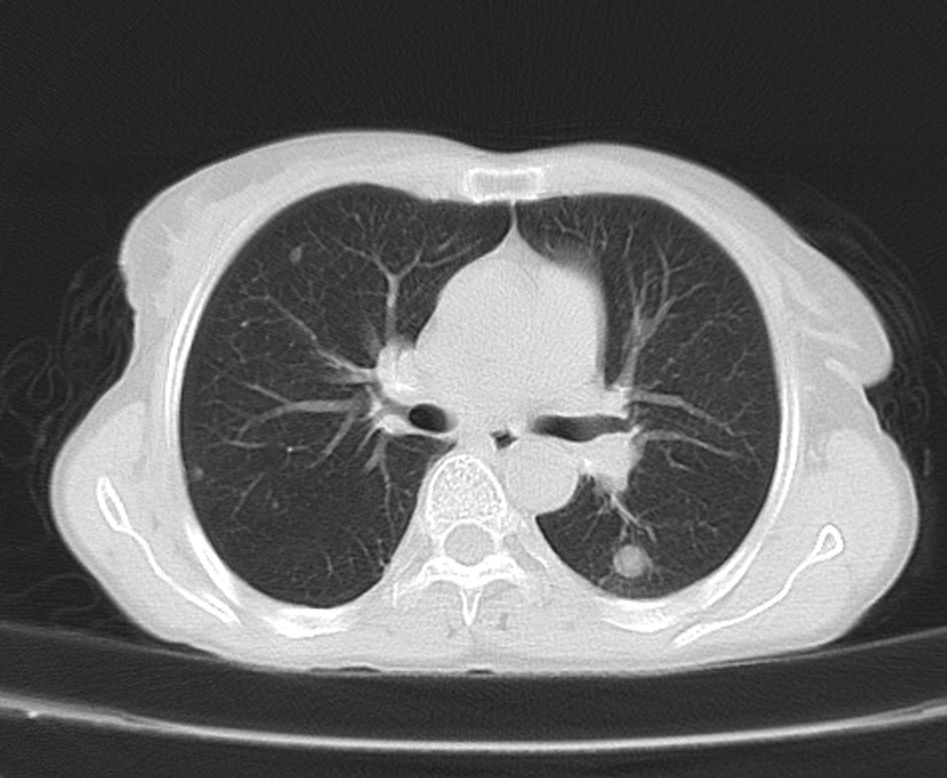

标题: CT21609:右乳包块1年,请各位讨论分析一下,乳腺CA, [打印本页]

标题: CT21609:右乳包块1年,请各位讨论分析一下,乳腺CA,

考虑---右乳癌并胸壁、肋骨、双肺转移。

考虑乳腺癌侵犯肋骨、胸壁及两肺转移可能性大。

右乳癌并胸壁、肋骨、双肺转移。

考虑右侧乳腺癌侵犯肋骨、胸壁及两肺转移。

支持考虑---右乳癌并胸壁、肋骨、双肺转移。

考虑右侧乳腺癌侵犯肋骨、胸壁及两肺转移可能。

考虑右侧乳癌并胸壁、肋骨及双肺多发性转移。